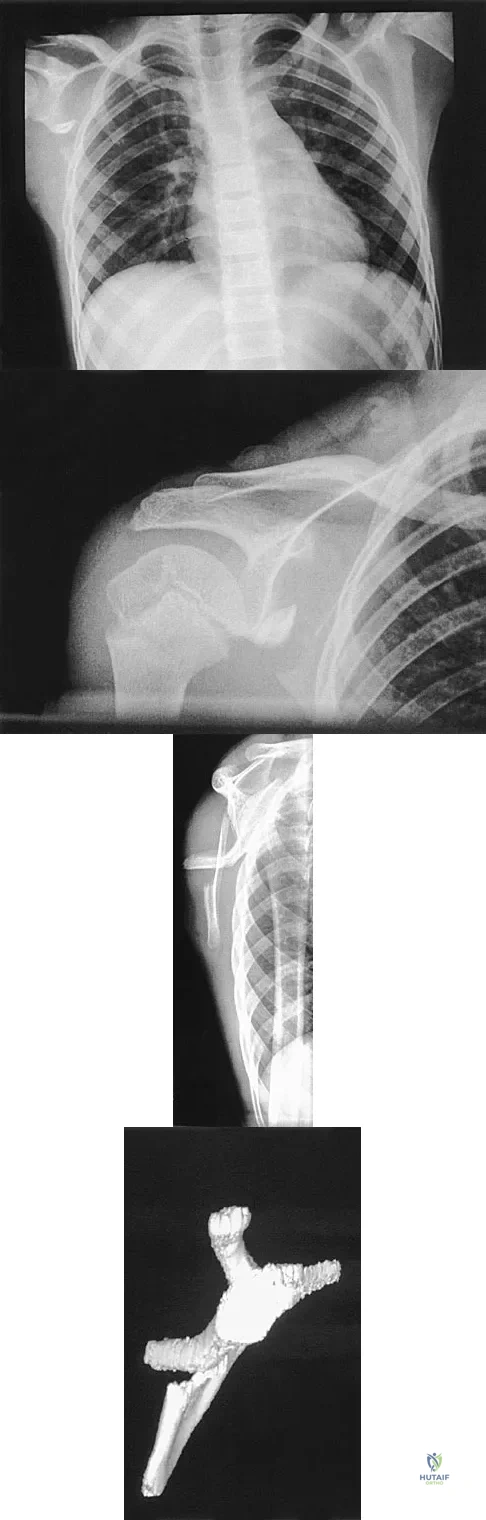

A 12-year-old boy has severe left shoulder pain after being struck by an automobile. A chest radiograph, AP and lateral radiographs, and a CT scan with three-dimensional reconstruction of the scapula are shown in Figures 38a through 38d. Management should consist of

Explanation